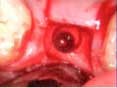

A 53-year-old female with a medical history of hypothyroidism, seasonal allergies, and asthma taking Synthroid and Singula presented to my office with pain in No. 3, failed root canal therapy, and a fracture. The tooth was deemed hopeless and extraction and implant placement was treatment planned. Under local anesthesia, tooth No. 3 was sectioned into three pieces and extracted. The sockets were debrided, filled with gel foam, and closed with chromic gut sutures. Healing was uneventful. The patient did not return for two years for follow-up. A CT scan was taken, which confirmed that approximately5 mm of bone remained below the floor of the sinus. After reviewing the options with the patient, a treatment plan of an internal sinus lift (osteotome), bone graft, platelet-rich fibrin (PRF) and simultaneous implant placement was agreed upon. Under local anesthesia, a full thickness flap with two vertical releasing incisions was performed at tooth No. 3 site. A trephine bur was used to a depth of 4 mm. An osteotome was then employed to infracture the bone core, which remained attached to the Schneiderman membrane. A bone graft consisting of DFDBA, anorganic bovine bone, and PRF was used in the osteotomy to increase the vertical bone height using sequential osteotomes. After sufficient elevation, a 7x9 tapered implant was placed on low speed to 50% of the implant depth. The remaining placement of implant was done with a hand torque on 50 ncm to allow for further expansion of the alveolar housing. A healing abutment was placed using the principles of platform switching. Healing was uneventful, and integration was successful.

Case 1: Implant and osteotome bone graft through the socket with Southern Implant